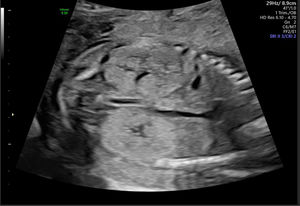

Figura 2.Displasia obstructiva alrededor de las 20 semanas de edad gestacional. Este feto masculino mostraba una obstrucción del tracto urinario inferior con riñones ecogénicos e hidrouréter severo; en esta imagen se visualiza y mide el riñón derecho. Imagen ecográfica del Centro Médico de la Universidad Erasmus.

Otro motivo de derivación podría ser la presencia de uno o más quistes renales, cuyo diagnóstico diferencial ecográfico incluye riñón displásico multiquístico (RDMQ), quistes renales simples y riñones poliquísticos. La localización del quiste dentro del riñón, el tamaño renal y el índice de líquido amniótico pueden ayudar a distinguir entre los diagnósticos. El RDMQ se presenta con múltiples quistes, por lo general unilaterales, en la corteza renal, ausencia de pelvis renal y sin parénquima renal normal visible por ecografía (fig. 3). Puede confundirse con hidronefrosis cuando los cálices dilatados simulan quistes grandes; sin embargo, la presencia de parénquima normal y una pelvis renal (dilatada) indica hidronefrosis. Los quistes renales simples pueden aparecer en etapas tempranas de la gestación y la mayoría se resuelven durante el embarazo12.